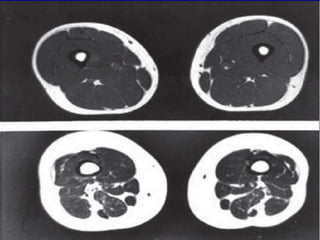

Cambios en la Composición

Corporal

 ↑ Tejido graso

 ↓ Tejido Magro

 ↓ Tejido Mineral

Óseo

 ↑ ECV, Obesidad,

Resistencia a la insulina,

DM II

 ↑ Sarcopenia, osteopenia,

osteoporosis

 ↑ incapacidad física,

mayor riesgo a caídas,

fracturas, > costos por

hospitalización, > riesgo

de complicaciones

Cambios en laComposición Corporal  ↑ Tejido graso  ↓ Tejido Magro  ↓ Tejido Mineral Óseo  ↑ ECV, Obesidad, Resistencia a la insulina, DM II  ↑ Sarcopenia, osteopenia, osteoporosis  ↑ incapacidad física, mayor riesgo a caídas, fracturas, > costos por hospitalización, > riesgo de complicaciones